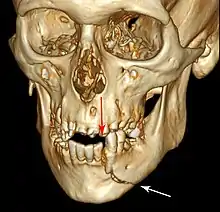

Essa lesão envolve o osso alveolar e pode se estender além do alvéolo. [7] [8] Existem 5 tipos diferentes de fraturas alveolares:

- Fratura da maxila: Fratura Le Fort, fratura zigomática, erupção orbital

- Fratura da mandíbula

Sinais de fratura dento-alveolar:

- Elementos dentários movendo-se juntos como um segmento e normalmente são deslocados.

- Hematomas na gengiva inserida.

- Gengiva em toda a linha de fratura frequentemente lacerada[9].

Investigação: Requer mais de uma visualização radiográfica para identificar a linha de fratura.

Tratamento: Reposicionar os dentes deslocados sob anestesia local e estabilizar o segmento móvel com uma tala por quatro semanas; suturar quaisquer lacerações de partes moles.